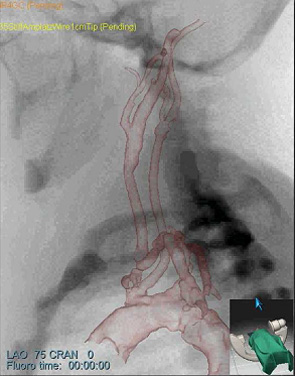

研究使用SimbionixANGO导师TM以色列dd站ANGO导师TM综合软件硬件内置模拟平台1a)模拟干扰程序基于诊断CTA和脉冲模拟模型支持实事求是插管操作反馈1b)并创建连续X射线成像、froscicC-arm定位和模拟反射剂注入2a-c)详情见http://www.simbionix.com

模拟模型直接转至SimbionixANGO导师TM模拟平台然后我们执行常用干预放射程序,如导管插入和操作、气球定位和放大,并插入病人专用模型微博2a-c显示样本快照模拟